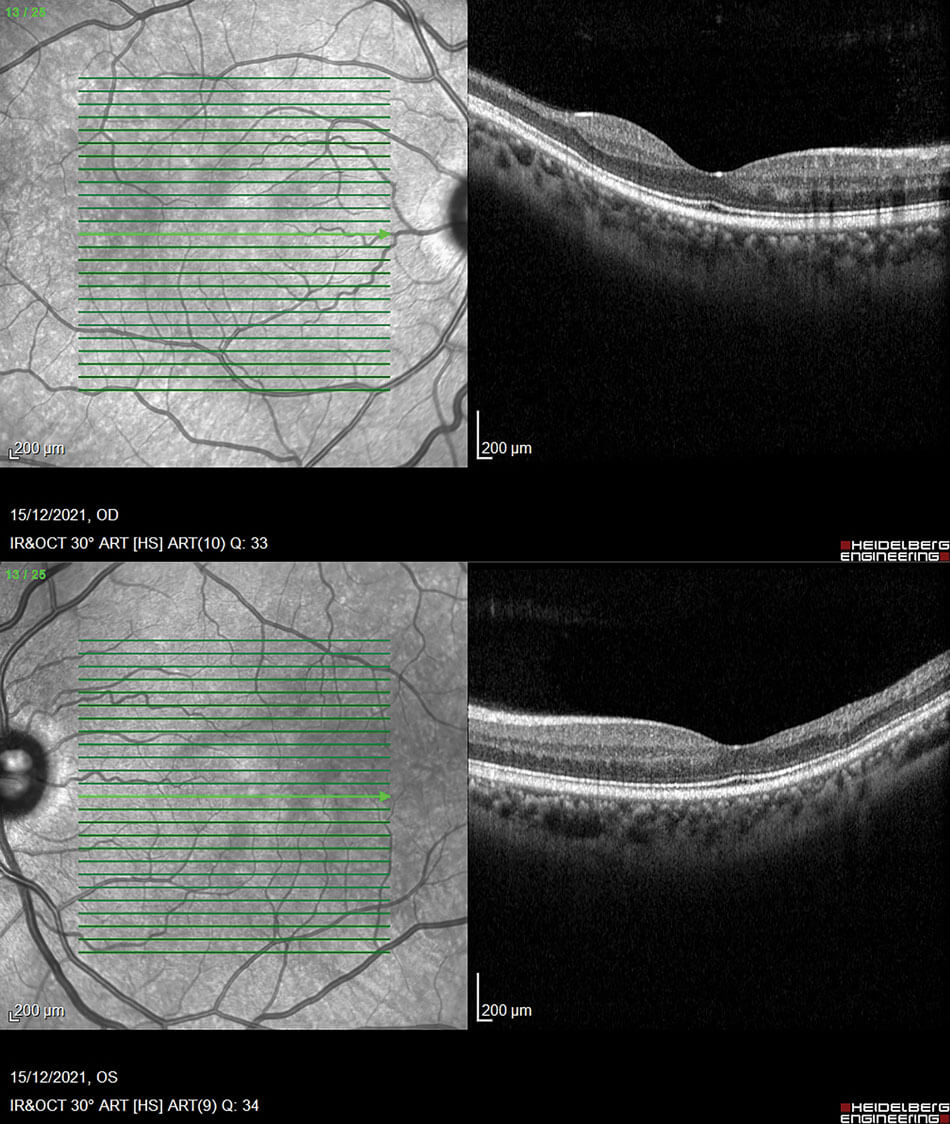

Figure 2: OCT’s of both eyes displaying macular thinning towards the temporal arcade and irregularity in the FAZ in RE.

The OCT’s of the RE and LE are shown in Figure 2. Both eyes show macular thinning in the nerve fibre layer leading into the inner nuclear and plexiform layers. The RE demonstrates irregularity in the foveal avascular zone. This is highlighted by how the layers thin out from the fovea towards the temporal arcade which corresponds to the Optos images with the ischaemia. Figure 3 shows the retinal thickness maps, and this thinning can be seen easily from the maps illustrated by the violet colour and the differential in the patterned ripple indentation line. The OCTA’s in Figure 4 highlight some capillary dropout shown in the deep capillary plexus within the foveal avascular zone, which could lead to some visual loss. This area should show capillaries, but the blackened area indicates the dropout which ties in with the retinal thickness map.